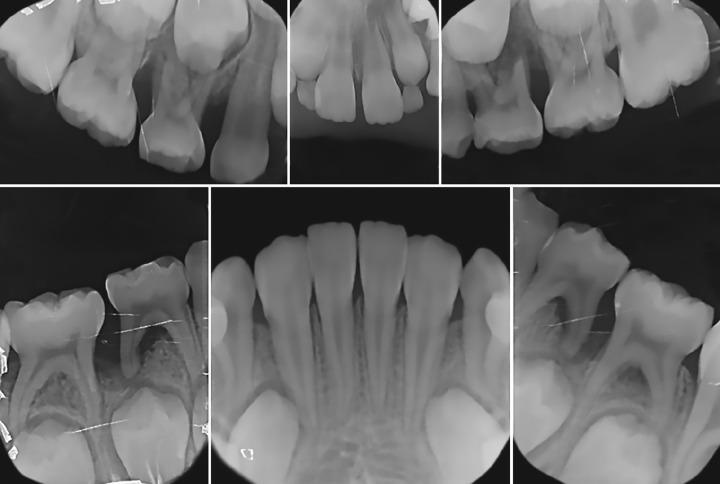

儿童原发性牙列局限性侵袭性牙周炎(LAP)是一种罕见疾病。LAP的主要特征是牙周袋深、骨质丧失、牙齿松动,有时还会出现牙齿自行脱落。LAP仅累及某些特定牙齿。Glanzmann血小板无力症(GT)是一种罕见的常染色体隐性出血性疾病。本文旨在介绍一名患有GT并出现LAP的5岁女孩病例,并讨论其临床管理。Prud'homme T、Roy E、Soueidan A、Fouassier M、Dajean-Trutaud S、Badran Z。一名患有Glanzmann血小板无力症的儿童诊断为局限性侵袭性牙周炎的多学科临床管理。《国际临床儿科牙科学杂志》2018年;11(4):344 - 348。

https://cdn.ncbi.nlm.nih.gov/pmc/blobs/4425/6212666/5e4481c32f3e/ijcpd-11-344-g001.jpg

https://cdn.ncbi.nlm.nih.gov/pmc/blobs/4425/6212666/63e579b8fce2/ijcpd-11-344-g002.jpg

https://cdn.ncbi.nlm.nih.gov/pmc/blobs/4425/6212666/530188dd4b5e/ijcpd-11-344-g003.jpg

https://cdn.ncbi.nlm.nih.gov/pmc/blobs/4425/6212666/ae98d286f7b0/ijcpd-11-344-g004.jpg

https://cdn.ncbi.nlm.nih.gov/pmc/blobs/4425/6212666/fd2a52a2b9fc/ijcpd-11-344-g005.jpg